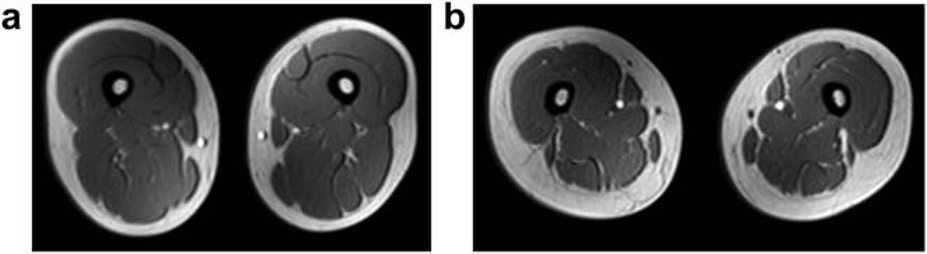

Figure: Representative magnetic resonance images of the femoral region in a female subject without non-alcoholic fatty liver disease (NAFLD) (a) and that in a female subject with NAFLD (b). The NAFLD subject had greater s.c. fat thickness, decreased muscle cross-sec-tion, and marbled muscles (steatosis) on the images.